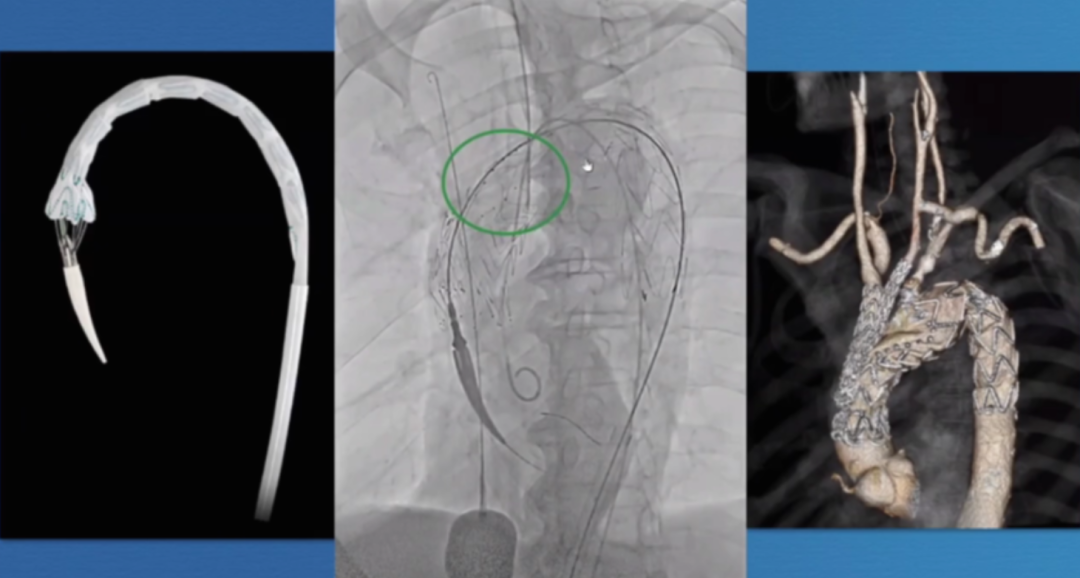

在近端密封区选择上,通常需向近端延伸25-30mm以实现更优密封效果,而定制器械凭借开窗设计,能有效增加密封长度。定制化支架技术也至关重要,支架必须精准定位,标记移动易引发开窗错位;同时要做好旋转控制,否则支架旋转不良会提升逆行夹层风险。一旦出现开窗对齐问题,可能导致I型内漏,且长期处理难度大,需借助更复杂的穿通技术纠正分支位置。

第二代分支支架在设计上进一步优化,Cook LSA分支支架(Gen2)采用三角形凹槽设计,要求左颈总动脉与左锁骨下动脉间距25mm,分支开口与织物端距离60mm,其预装导管系统使分支接入更简便,为临床操作提供了便利。

在主动脉介入治疗领域,支架设计持续创新。Terumo双分支支架采用大型矩形凹槽设计,即便旋转90度,仍能顺利接入分支,对于弓部曲线较为紧张的情况适配性更强。不过,该支架也面临技术挑战,手术中需要精准控制支架的旋转与对齐,以确保治疗效果。

深圳设计的支架同样亮点十足。它具有短输送尖端的特点,无需跨越主动脉瓣,部署过程简单,且不需要进行严格的血压控制。支架配备两个平行侧支,搭配低剖面8-9F桥接支架,在接入方式上,采用右臂入路结合左颈动脉小切口的方式,为手术操作提供了便利,也有望为患者带来更优的治疗体验。